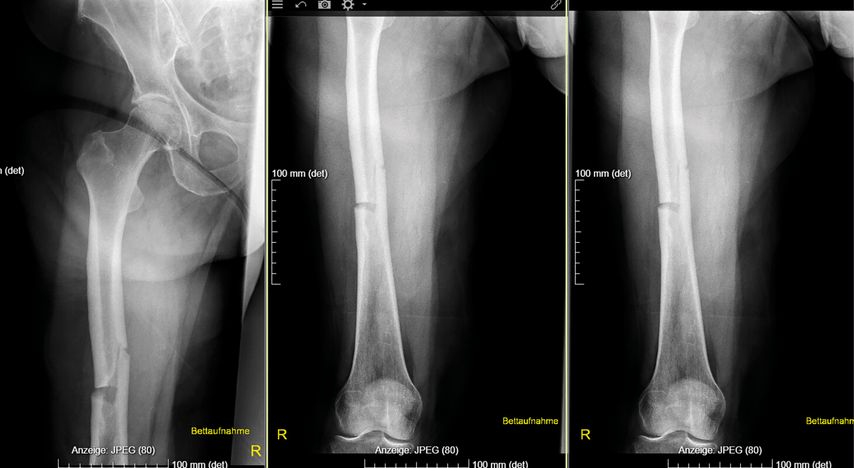

Eine Analyse der Femurfraktur in der Anamnese zeigte, dass es sich dabei um keine typische osteoporotische Fraktur am Femurhals, sondern um eine atypische Fraktur am Femurschaft unter Bisphosphonattherapie gehandelt hatte, wofür eine gerade Frakturlinie auf der lateralen und eine schräge Frakturlinie auf der medialen Seite sprachen (Abb.1).1 Der Fraktur waren keine Schmerzen vorausgegangen; diese gelten als Warnsignal für atypische Frakturen.2 Werden Patient:innen unter antiresorptiver Therapie mit unbestimmten Knochenschmerzen an den Oberschenkeln vorstellig, so sollte man hellhörig werden, erläuterte Rintelen.

Abb. 1: Die Röntgenaufnahmen zeigen eine atypische gerade Frakturlinie auf der lateralen und eine schräge Frakturlinie auf der medialen Seite